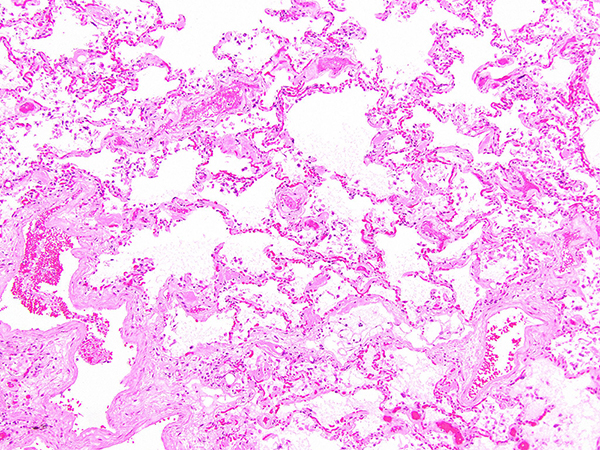

Clinical History: A 67-year-old man with a history of coronary artery disease, obstructive sleep apnea and morbid obesity sustained a right femur fracture after a fall. He underwent orthopedic surgery and had a complicated postoperative period due to respiratory insufficiency and ventilator dependance, from which he never recovered. The patient expired shortly thereafter due to respiratory failure due to diffuse alveolar damage (DAD). Representative sections of the lung from areas less involved by DAD are shown in Figures 1 through 6. A Congo red stain is shown in Figures 4 and 5 (the latter under polarized light). A representative section of the heart is shown in Figure 6.

This case depicts an example of diffuse alveolar septal amyloidosis, characterized by the abnormal deposition of amyloid within alveolar septa and vessel walls. It occurs most frequently in patients with known systemic amyloidosis, but can rarely occur in patients without a prior history of extrapulmonary disease. On routine histologic sections, lung architecture is preserved with the characteristic appearance of variably thickened alveolar septa, with some areas being almost normal and others being expanded by amyloid deposits, including amyloid deposition within vessel walls. Amyloid can be differentiated from collagen deposition (interstitial fibrosis) since the former has an amorphous appearance. Involvement of blood vessels in amyloidosis is another clue to the diagnosis. Lastly, amyloid deposits are congophilic with apple-green birefringence under polarized light, which confirms the diagnosis. Immunostains to subtype the amyloid protein can be attempted, but are very difficult to interpret because of high background. Currently, mass spectometry is considered the most accurate method to subtype amyloid.